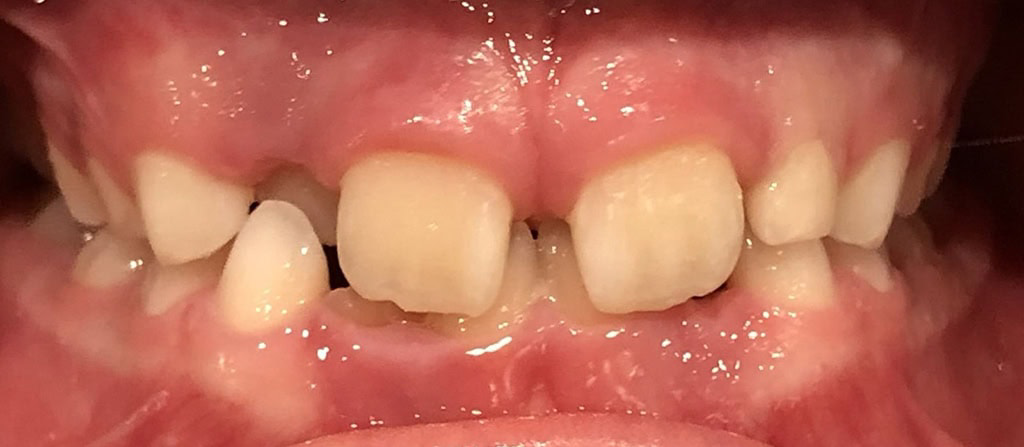

Actual Patient: Alexander

Alexander Before 4 Alexander After 4

Severe “Underbite”, Narrow Jaws, Adult Teeth Not Growing In

Alexander Before 1 Alexander After 1

Front View

Top View

Right & Left Sides